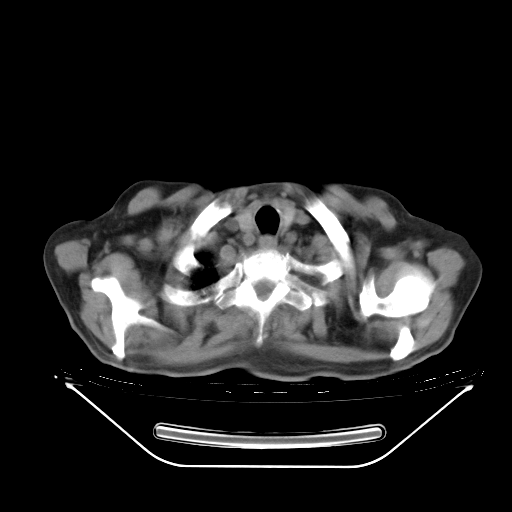

今天复查肺部CT,发现双肺广泛磨玻璃样改变。所以我把3月19日和5月9日相隔50天的肺部CT上传。请大家会诊。

5月9日肺部CT(在4月27日齐鲁医院肺部CT描述部分肺组织磨玻璃样改变,12天后肺组织广泛磨玻璃样改变)

大致读了系列胸部CT:纵隔窗无明显异常,肺窗:从4、27至今:主要是双肺中下野外带可见毛玻璃样改变,目前处于急性肺泡炎阶段,至于原因考虑1、结替组织或胶原血管性疾病所致?2、恶性疾病如恶组在肺部所致的表现或细支气管肺泡癌?3、药物或其它原因如肺蛋白沉着症所致肺泡炎目前不太可能?总之,明天就去请我院的呼吸科、感染科、血液科和临免专家会诊哈。